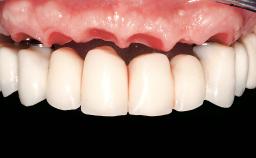

An 83-year-old male patient requested treatment for his existing maxillary complete overdenture and mandibular complete denture. He reported no general medical conditions of significance that would affect his dental treatment and was taking no prescription medication. He denied suffering from oral pain and displayed no evidence of parafunctional habits or temporomandibular joint disorder. Oral and radiographic evaluation revealed two retained maxillary teeth (13 and 15) supporting prefabricated ballshaped attachments. Both teeth were mobile and associated with active periodontal disease and extensive dental caries; these were considered non-restorable and were recommended for extraction. The patient’s existing complete maxillary and mandibular prostheses were approximately 2 years old. He was very satisfied with the appearance of both prostheses. His chief complaint was related to the instability and lack of retention associated with the existing mandibular prosthesis.